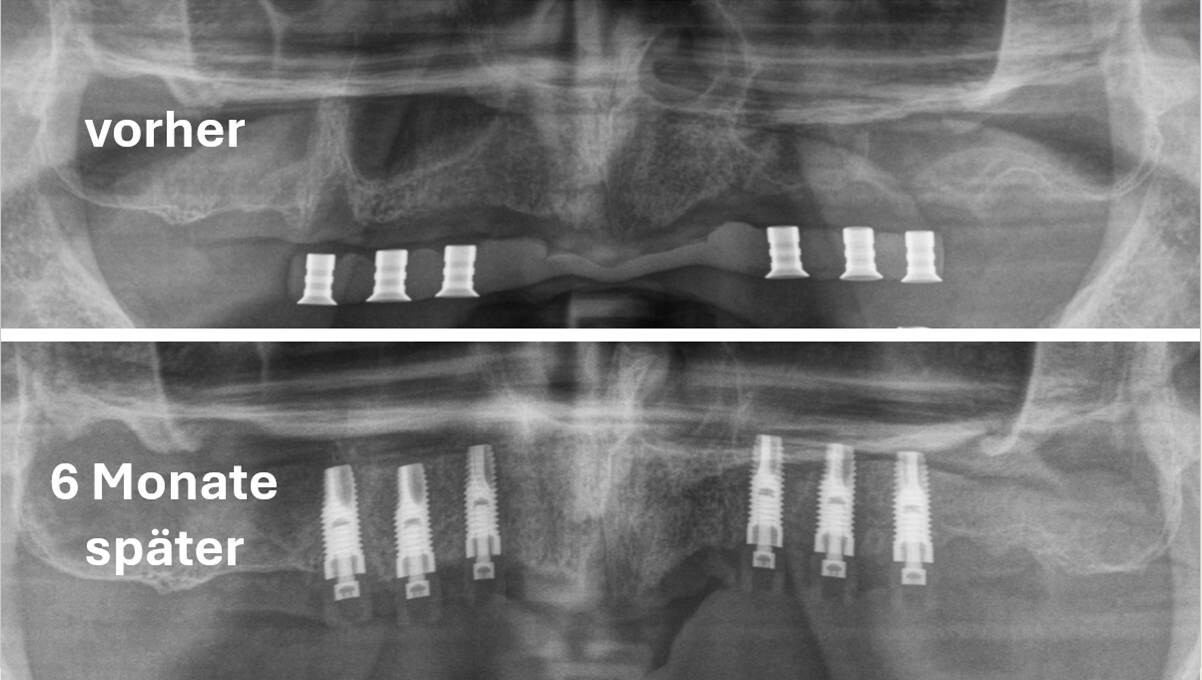

Biologisches Konzept des autologen, einzeitigen Sinuslifts

- Autologer Knochen als biologischer Stimulus statt Knochenersatzmaterial

- Implantat als Space Maintainer: Biologie statt Volumenauffüllung

Chirurgische Umsetzung & klinische Realität

- OP-Technik Step by Step: vom Zugang bis zum Wundverschluss

- Klinische Fälle, OP-Videos und typische Fehler (inkl. Grenzfälle)